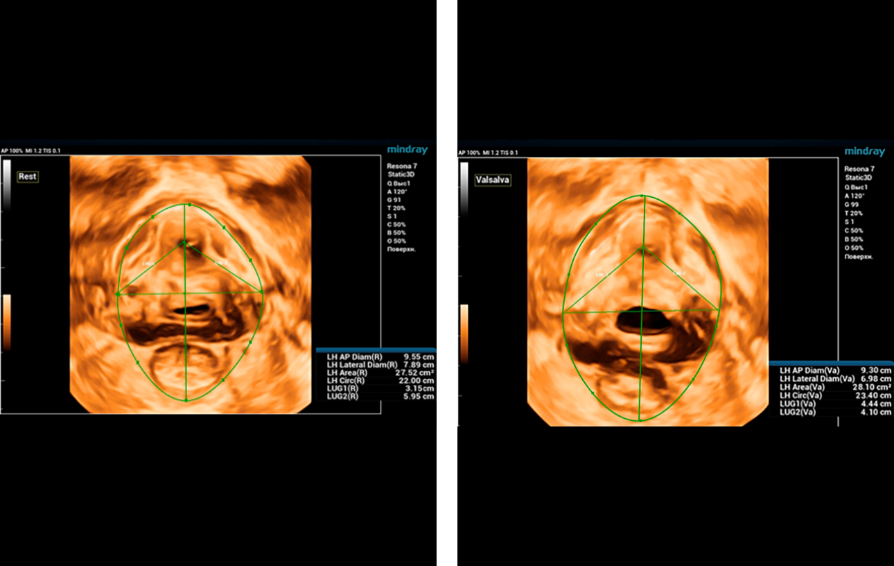

During ultrasound examination using Endocavity volume convex array transducer (DE10-3WU, Resona 7, Mindray), tearing of both levator ani muscles on the right and left is visualized, thinning of the tendon center of the perineum to 3-4 mm, the distance LH (levator hiatus) is increased ŌĆō 6.13 cm, LUG1 ( One side of the levator-urethra gap) ŌĆō 2.95 cm and LUG2 ŌĆō 3.15 cm (normally less than 2.5 cm)